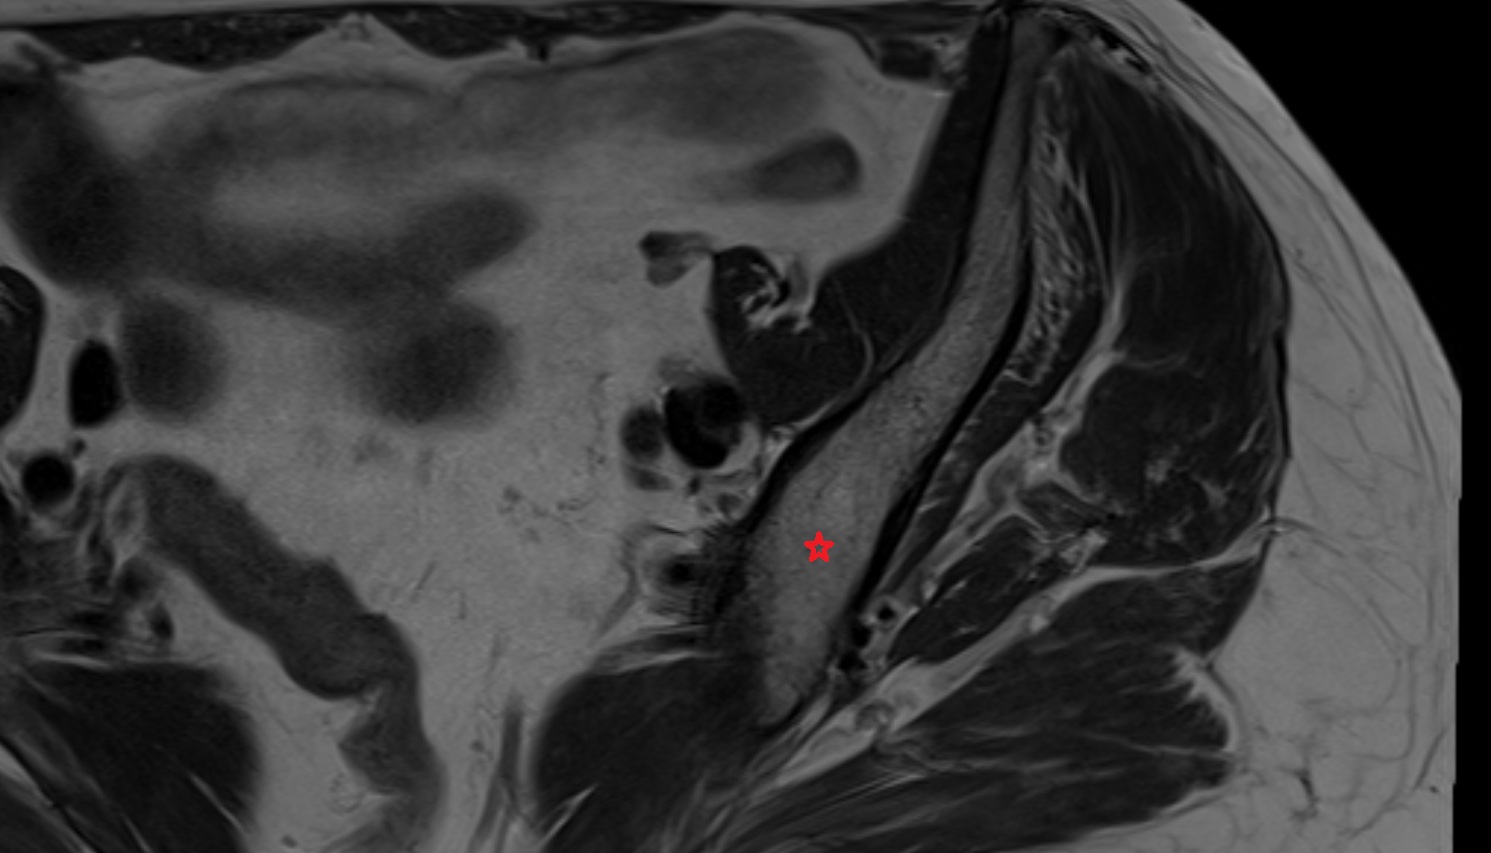

- Rectum

- Urinary bladder

- Uterus

- Cervix of uterus

- Vagina